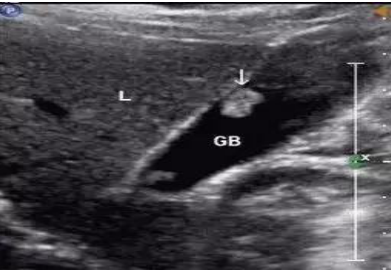

胆囊息肉大部分可无临床症状,很多患者仅是在体检时通过超声检查发现病变。部分患者可伴随包括上腹部隐痛、腹胀及恶心、食欲不振等消化道症状。超声检查就可以明确胆囊息肉的大小、位置、数量以及囊壁的情况,而且价格低廉,是确诊胆囊息肉的理想检查手段。

▲ 超声下胆囊息肉